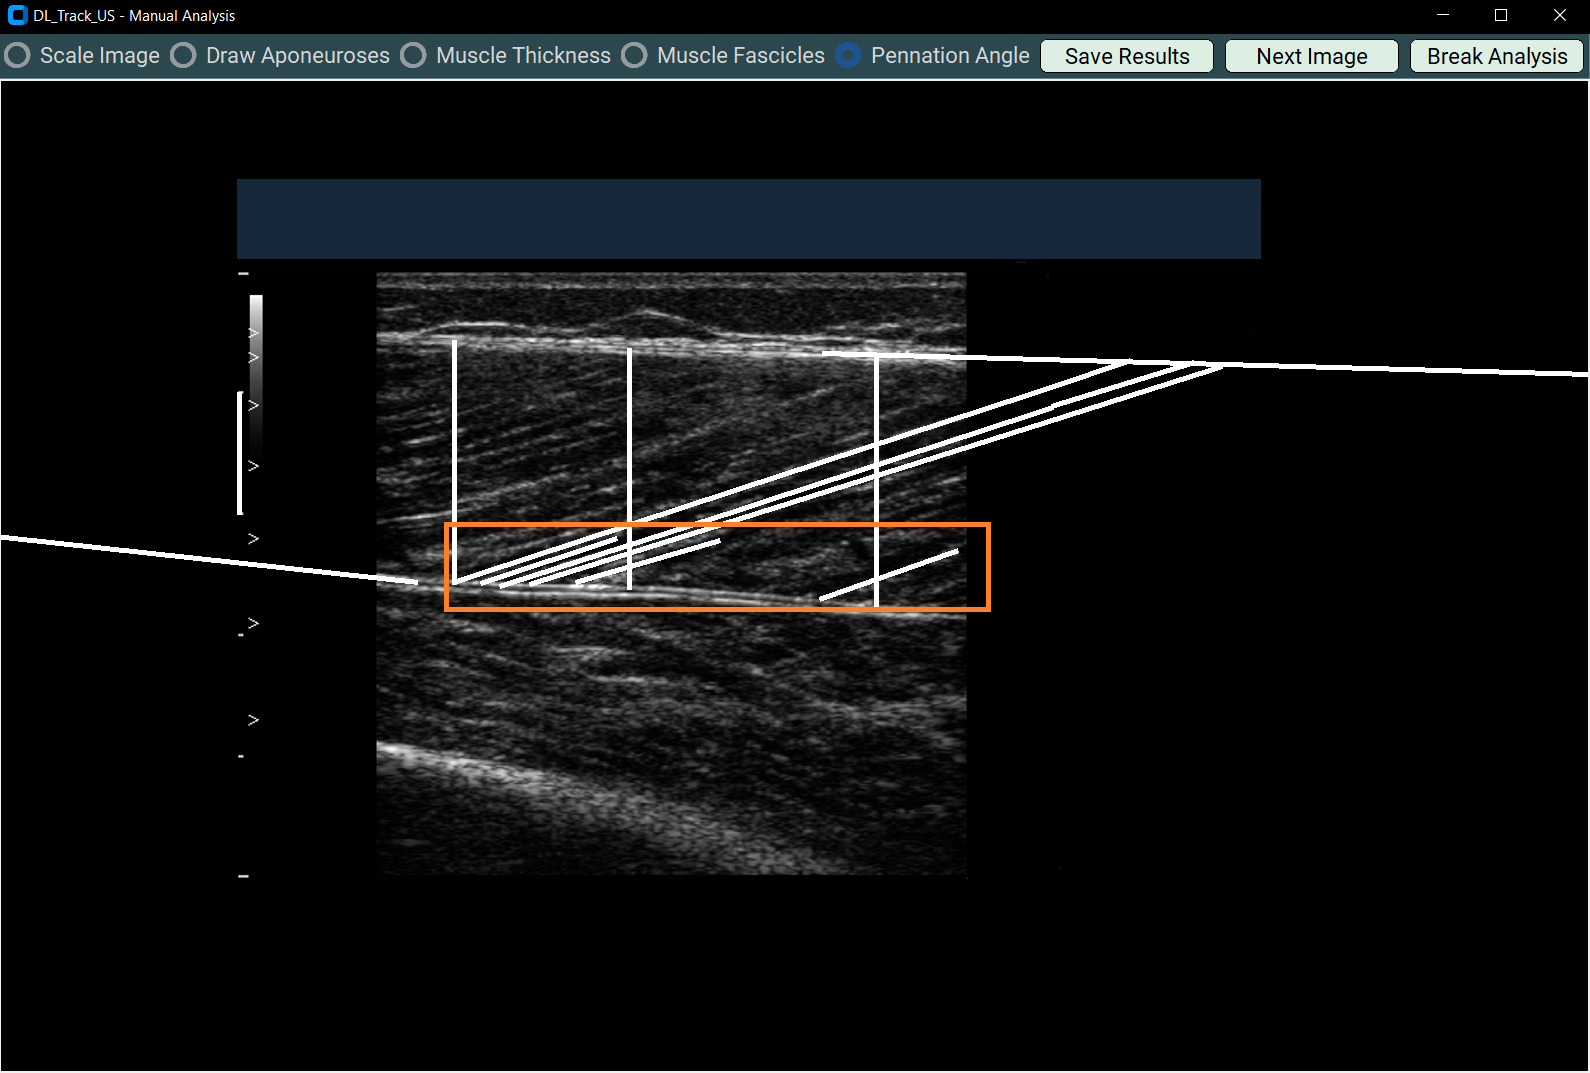

4.5 Measuring Pennation Angles¶

- Select Pennation Angle.

- Draw at least three pennation angles:

- Each must have two segments:

- Along the fascicle

- Along the deep aponeurosis